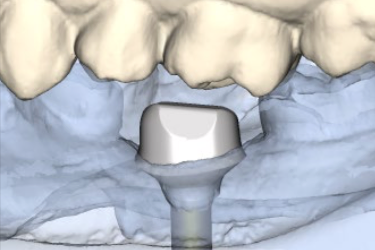

Atlantis

Dentsply Implant

Des piliers d'implants usinés avec profil d'émergence anatomique. Emplacement des implants en prévision de la restauration finale!